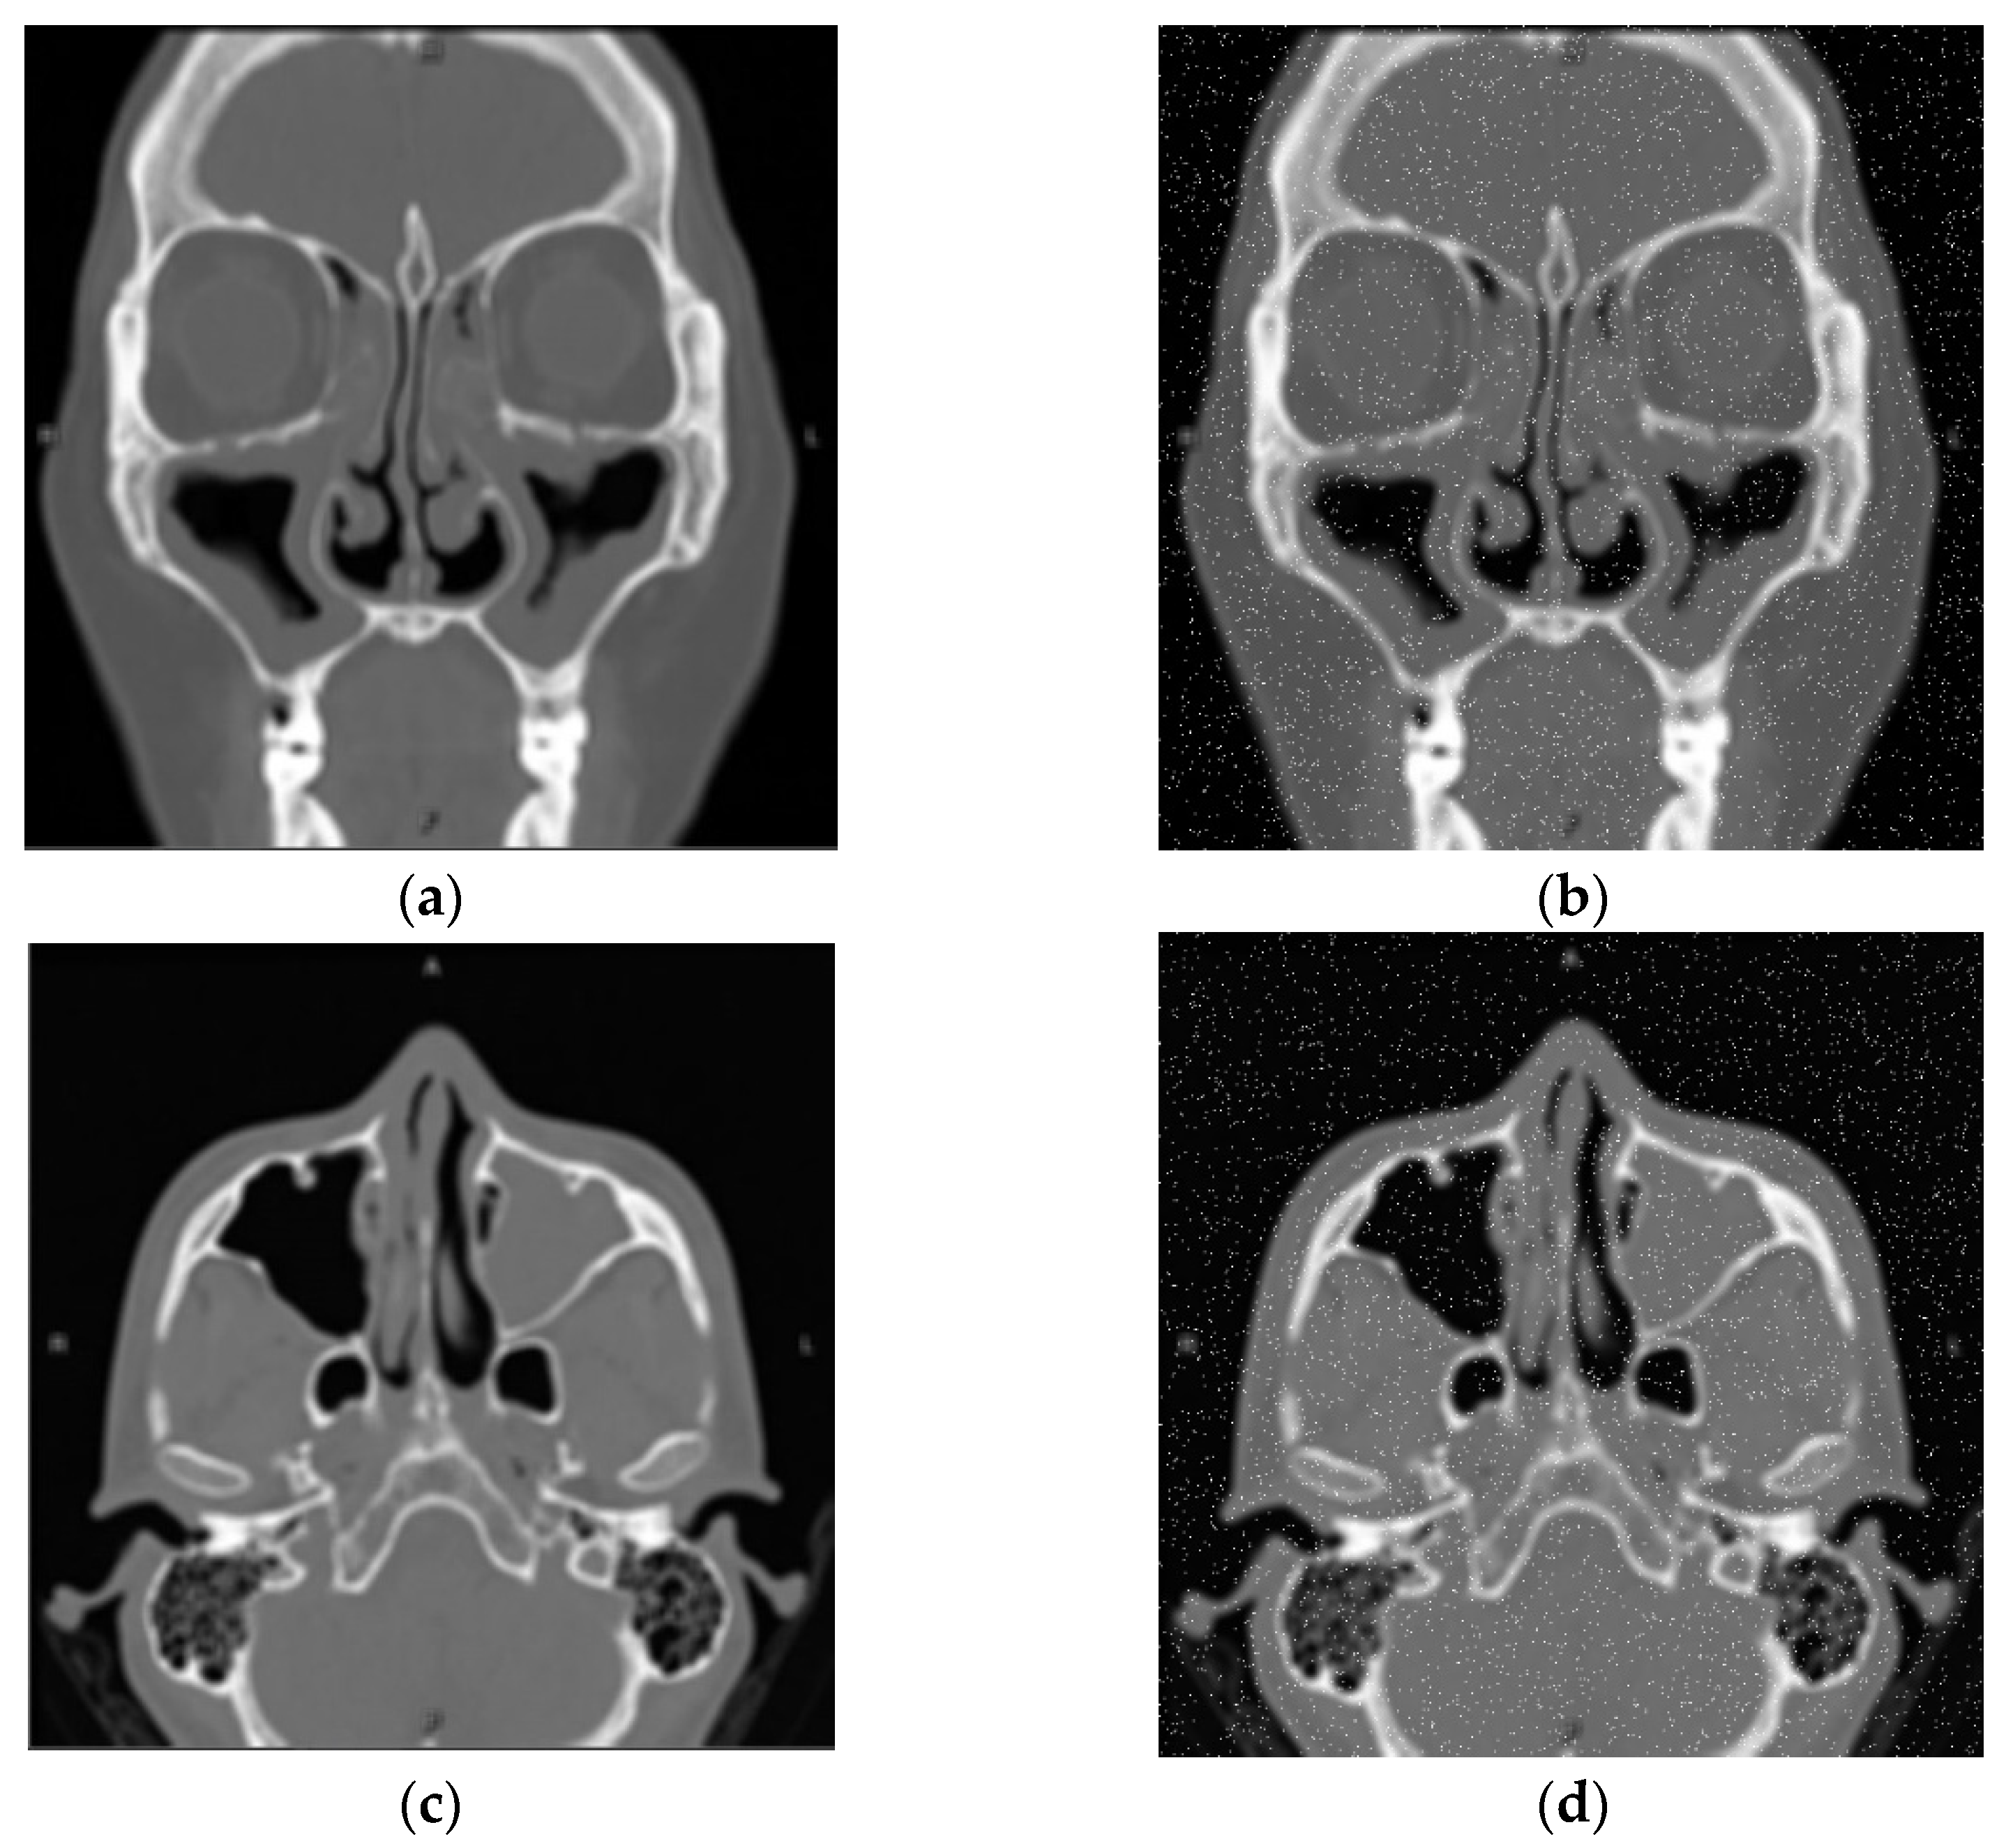

3.4.1. Morphology